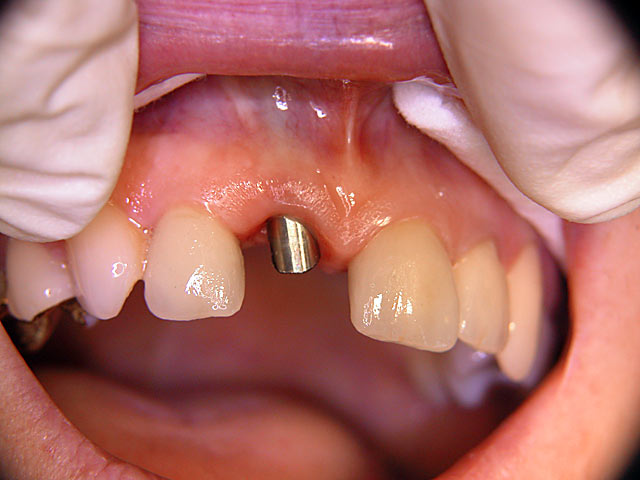

Die folgenden Patientenfälle sollen Ihnen einen Einblick in die Möglichkeiten der modernen Implantation geben.

Sofort-Implantation: